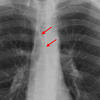

Pericardial stripe